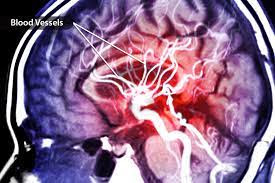

Do You Think Stress Alone Can Cause a Stroke?

My stroke was inherited, a Protein S deficiency which causes blood clots. And you probably know the rest and the reason this blog came about.

I've been quite stressed lately because I've been inside, no thanks to the pandemic, and I thought, bordering on overthinking, would stress give a person a stroke? Or a second stroke?

Most people already understand that high blood pressure, high cholesterol, and smoking increase a person’s risk of stroke. But without those negative situations, can plain old stress cause a stroke? Unfortunately, studies have shown so, all around the world. Just a sampling....